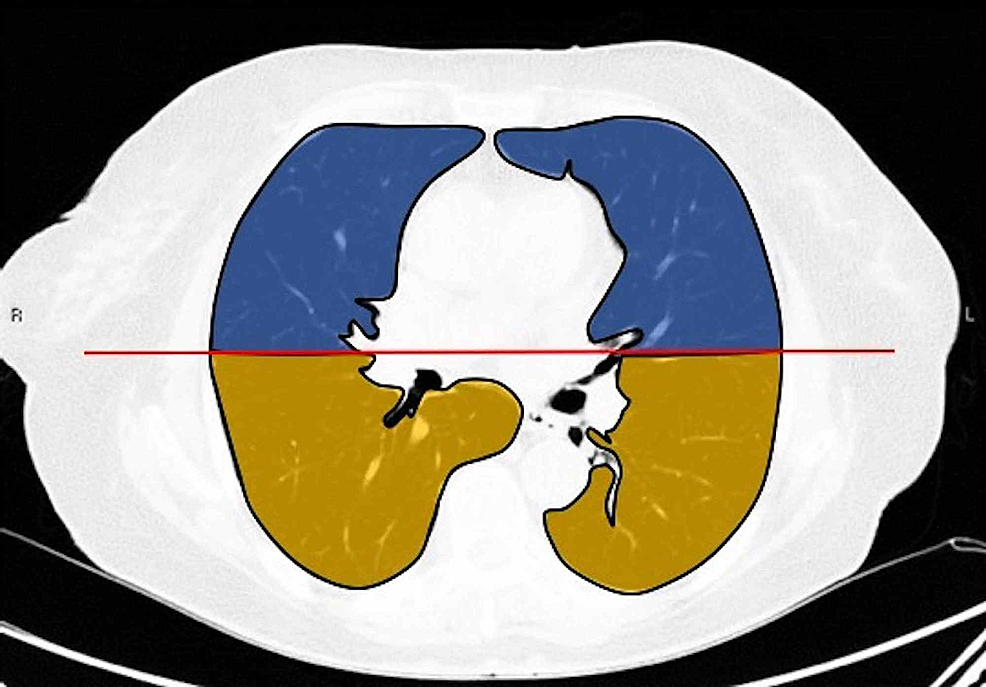

Two board-certified radiologists (E.P. and U.M., with 25 and five years of experience, respectively) reviewed the chest CT images on a picture archiving and communication system (PACS, Carestream Health, Inc, Rochester, NY). Chest CT images were evaluated with both mediastinal (width: 350 HU, level: 40 HU) and lung (width: 1500 HU, level: -500 HU) window level settings. The two radiologists identified pulmonary lesions based on their density, shape, and margin. The locations of the lung lesions were recorded as lobar, axial, anterior, and posterior. Axial locations were categorized as central (inner two-thirds of the lung) or peripheral (outer one-third of the lung). Each lung was divided by an axial line into anterior and posterior halves (Figures 2, 7). The densities of the patchy-confluent lesions were classified as pure GGO, pure consolidation, or mixed. Nodular lesion densities were classified as pure GGO, solid, or partly solid. Margins were classified as well-defined or ill-defined. As most of the lesions were patchy, confluent, and ill-defined margins, lesion sizes were not assessed. Instead, a visual severity score, which was slightly modified from Pan et al., ranging from 0 to 4 for each individual lobes was calculated. Each of the five lung lobes was visually scored on a scale of 0 to 4 as follows: 0: no involvement; 1: less than 25% involvement; 2: 25-50% involvement; 3: 50-75% involvement; and 4: 75-100% involvement.

The total CT score was the sum of all individual five lobar scores ranging from 0 (no involvement) to 20 (maximum involvement).